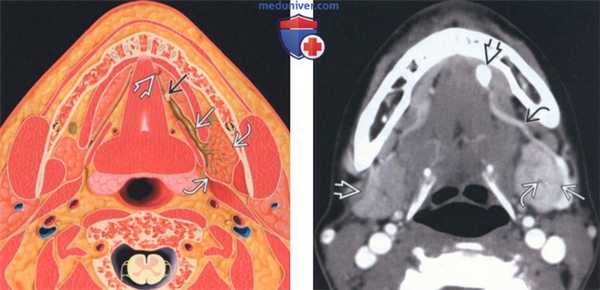

(Слева) На аксиальном рисунке показан конкременты в дистальных отделах протока поднижнечелюстной железы сразу же перед сосочком. Проксимальные отделы протока и третичные протоки расширены. Поднижнечелюстная железа (ПНЖ) воспалена и увеличена.

(Справа) На аксиальной КТ с КУ определяется асимметричное контрастное усиление увеличенной левой ПНЖ по сравнению с правой. В дистальных отделах протока поднижнечелюстной железы визуализируется конкремент на уровне протокового сосочка. Определяется лишь легкое расширение протока в области ворот. Также видны расширенные сосуды дна полости рта.